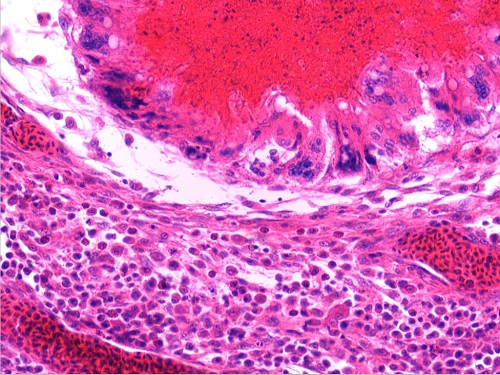

淋巴结大肠杆菌肉芽肿3(有大量浆细胞)